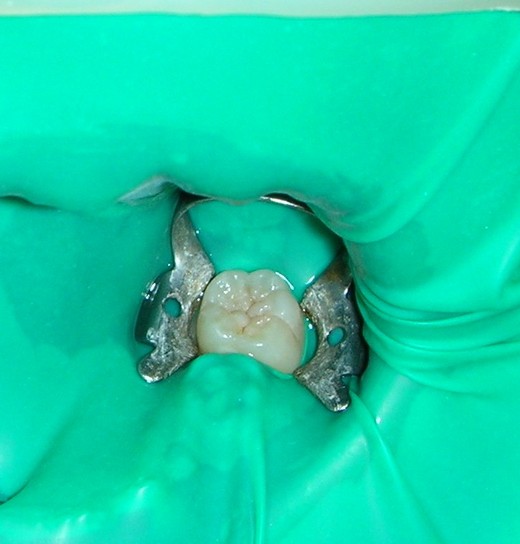

它能夠流入溝隙中把溝隙封填起來,堵住溝隙開口,不再讓食物殘屑與細菌陷入其中,並使咬合面變得平滑,好像塗了一層鐵弗龍一般,非常容易清潔(圖3);因此發生蛀牙的必要病因:蛀牙菌與糖分(來自飲食)被「溝隙封填劑」給阻斷,因而能預防止蛀。

5. 塗佈液態的溝隙封填劑,以光照硬化,硬化之後通常是呈乳白色,利於日後觀察封填劑 存在的狀況